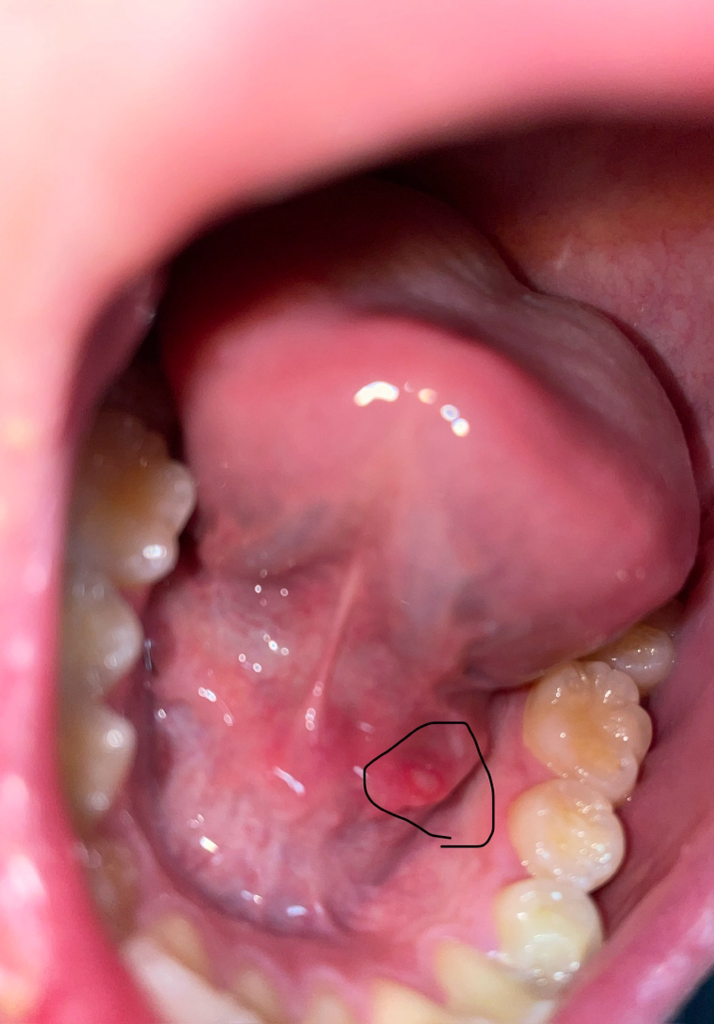

입안 혀아래쪽 수포?염증? 뭐가났어요

저거 생긴진 4일정도됬는데 평상시에 좀 이물감이라던지 밥먹을 때 불편감이 좀 있어서 질문드립니다. 저거 뭔가요? 없애는 방법은 뭐구요..

• 2번 째 사진

• 안녕하세요. 이송재 의사입니다. 사진으로 보았을 때는 구내염으로 생각 됩니다. 궤양성 병변이기 때문에 시간이 지나면 낫지만, 통증이 동반되고 증상이 있다면 가까운 약국에서 알보칠 구매해서 발라 보시기 바랍니다.